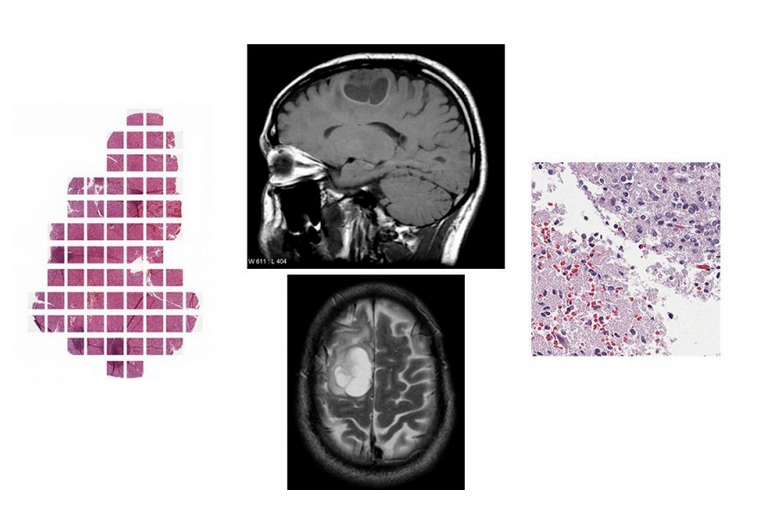

Digital Pathology

• Regions of Interest specification

• Background nuclei segmentation

• Nuclei features extraction

• Tumor classification

Types of Glioma

I - Pilocytic astrocytoma

II - Low-grade glioma

III - Malignant glioma Glioblastoma multiforme (GBM)

MRI